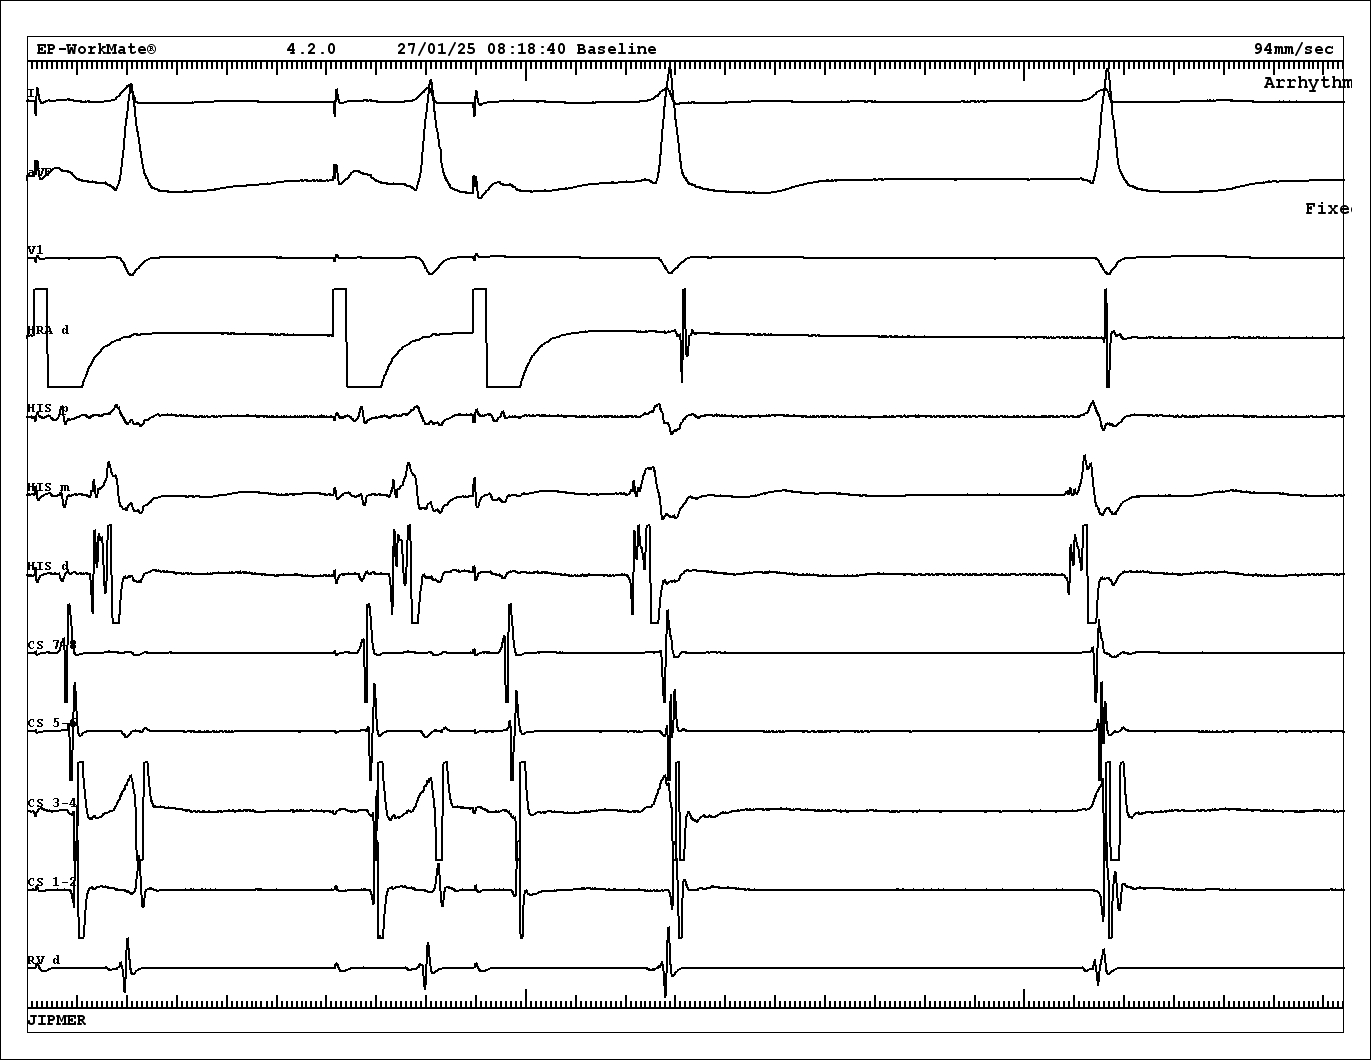

Case 2 - 42 F - Tachy induced with A extra. VA 126

tachy.jpg

PVC on time with His

pvc.jpg

VOP from base - cPPI-TCL 140 ms

vop_base.jpg

VOP from apex - cPPI-TCL 180 ms

vop.jpg

VA from base and apex

va_base_apex.jpg

Diagnosis

• Atypical AVNRT

• Bystander concealed nodoventricular AP

• Successful ablation at RIE